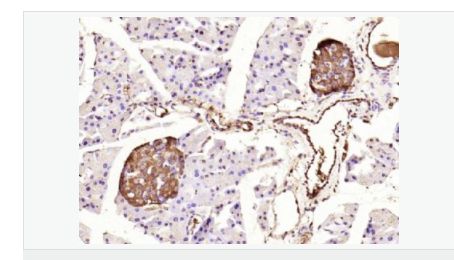

交叉反應(yīng):Human,Mouse,Rat(predicted:Dog,Pig,Cow,Rabbit,Sheep,GuineaPig) 推薦應(yīng)用:IHC-P,IHC-F,ICC,IF,Flow-Cyt,ELISA

| 產(chǎn)品應(yīng)用 | ELISA=1:5000-10000 IHC-P=1:100-500 IHC-F=1:100-500 Flow-Cyt=1ug/Test ICC=1:100-500 IF=1:100-500 (石蠟切片需做抗原修復(fù)) not yet tested in other applications. optimal dilutions/concentrations should be determined by the end user. |

| 免 疫 原 | KLH conjugated Synthesised phosphopeptide derived from human IRS1 around the phosphorylation site of Tyr632:GD(p-Y)MP |

| 產(chǎn)品介紹 | Insulin receptor substrates (IRS) are responsible for several insulin related activities, such as glucose homeostasis, cell growth, cell transformation, apoptosis and insulin signal transduction. Serine/threonine phosphorylation of IRS1 has been demonstrated to be a negative regulator of insulin signaling and is responsible for its degradation, although IRS1 degradation pathways are not well understood. IRS1 has also been shown to be constitutively activated in cancers such as breast cancer, Wilm's tumors, and adrenal cortical carcinomas, thus making IRS1 phosphorylation and subsequent degradation an attractive therapeutic target. To date there have been four subtypes identified: IRS1, 2, 3 and 4, with IRS1 being widely expressed. Function: May mediate the control of various cellular processes by insulin. When phosphorylated by the insulin receptor binds specifically to various cellular proteins containing SH2 domains such as phosphatidylinositol 3-kinase p85 subunit or GRB2. Activates phosphatidylinositol 3-kinase when bound to the regulatory p85 subunit. Subunit: Interacts with UBTF and PIK3CA (By similarity). Interacts (via phosphorylated YXXM motifs) with PIK3R1 (By similarity). Interacts with ROCK1 and FER (By similarity). Interacts (via PH domain) with PHIP (By similarity). Interacts with GRB2 (By similarity). Interacts with SOCS7. Interacts (via IRS-type PTB domain) with IGF1R and INSR (via the tyrosine-phosphorylated NPXY motif). Interacts with ALK. Interacts with EIF2AK2/PKR (By similarity). Subcellular Location: Membrane; Single-pass type I membrane protein. Tissue Specificity: Isoform Long and isoform Short are predominantly expressed in tissue targets of insulin metabolic effects: liver, adipose tissue and skeletal muscle but are also expressed in the peripheral nerve, kidney, pulmonary alveoli, pancreatic acini, placenta vascular endothelium, fibroblasts, monocytes, granulocytes, erythrocytes and skin. Isoform Short is preferentially expressed in fetal cells such as fetal fibroblasts, muscle, liver and kidney. Found as a hybrid receptor with IGF1R in muscle, heart, kidney, adipose tissue, skeletal muscle, hepatoma, fibroblasts, spleen and placenta (at protein level). Overexpressed in several tumors, including breast, colon, lung, ovary, and thyroid carcinomas. Post-translational modifications: Serine phosphorylation of IRS1 is a mechanism for insulin resistance. Ser-312 phosphorylation inhibits insulin action through disruption of IRS1 interaction with the insulin receptor (By similarity). Phosphorylation of Tyr-896 is required for GRB2-binding (By similarity). Phosphorylated by ALK. Phosphorylated at Ser-270, Ser-307, Ser-636 and Ser-1101 by RPS6KB1; phosphorylation induces accelerated degradation of IRS1. DISEASE: Polymorphisms in IRS1 may be involved in the etiology of non-insulin-dependent diabetes mellitus (NIDDM) [MIM:125853]. Similarity: Contains 1 IRS-type PTB domain. Contains 1 PH domain. SWISS: P35568 Gene ID: 3667 Database links: Entrez Gene: 3667 Human Omim: 147545 Human SwissProt: P35568 Human Unigene: 471508 Human Important Note: This product as supplied is intended for research use only, not for use in human, therapeutic or diagnostic applications. |